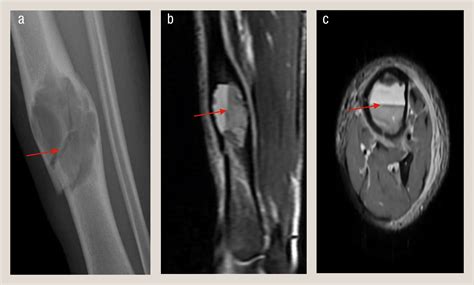

• Imaging Tests: Imaging tests, such as X-rays, CT scans, or MRI scans, can provide detailed images of the bone and surrounding tissues. These tests help identify the cause of the lump and determine its extent.

• Bone Tumors: These can be either benign (non-cancerous) or malignant (cancerous). Benign tumors, such as osteochondromas or enchondromas, are generally harmless but can cause discomfort or affect mobility. Malignant tumors, like osteosarcoma, are more serious and require immediate medical attention.

• : Bone cysts, such as aneurysmal bone cysts, can develop within the tibia and appear as lumps. These cysts are usually benign but can cause pain and weaken the bone.

• Biopsy: In some cases, a biopsy may be necessary to obtain a sample of the lump for further analysis. This involves removing a small piece of tissue, which is then examined under a microscope to determine if it is benign or malignant.